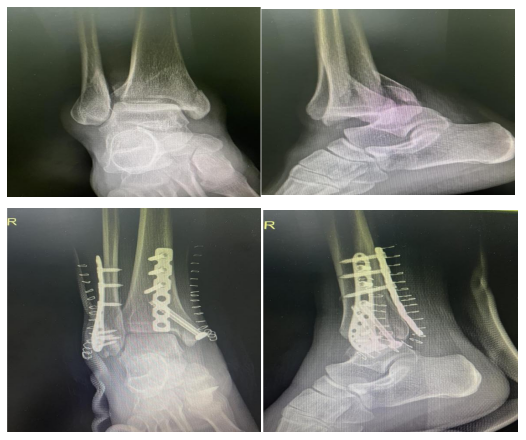

最近,苏州高新区人民医院骨科贾鹏主任医师接诊了一位特殊的患者——小王在下楼梯时不慎崴脚,脚踝迅速肿胀、关节明显畸形。凭借此前了解的急救知识,她立即用硬纸板临时固定伤处,毛巾裹冰袋冷敷、患肢抬高20厘米,家人紧急送医后,拍片确诊为踝关节骨折。得益于前期科学处理,贾鹏主任及时为患者实施了手术,目前小王已康复出院。

崴脚后应尽快到骨科就诊,医生会通过体格检查+X光/CT/MRI,明确是韧带损伤、骨折还是关节不稳。像小王这类患者,若早期未正确固定、勉强行走,易导致骨折移位,若处理及时,部分骨折可避免手术创伤。